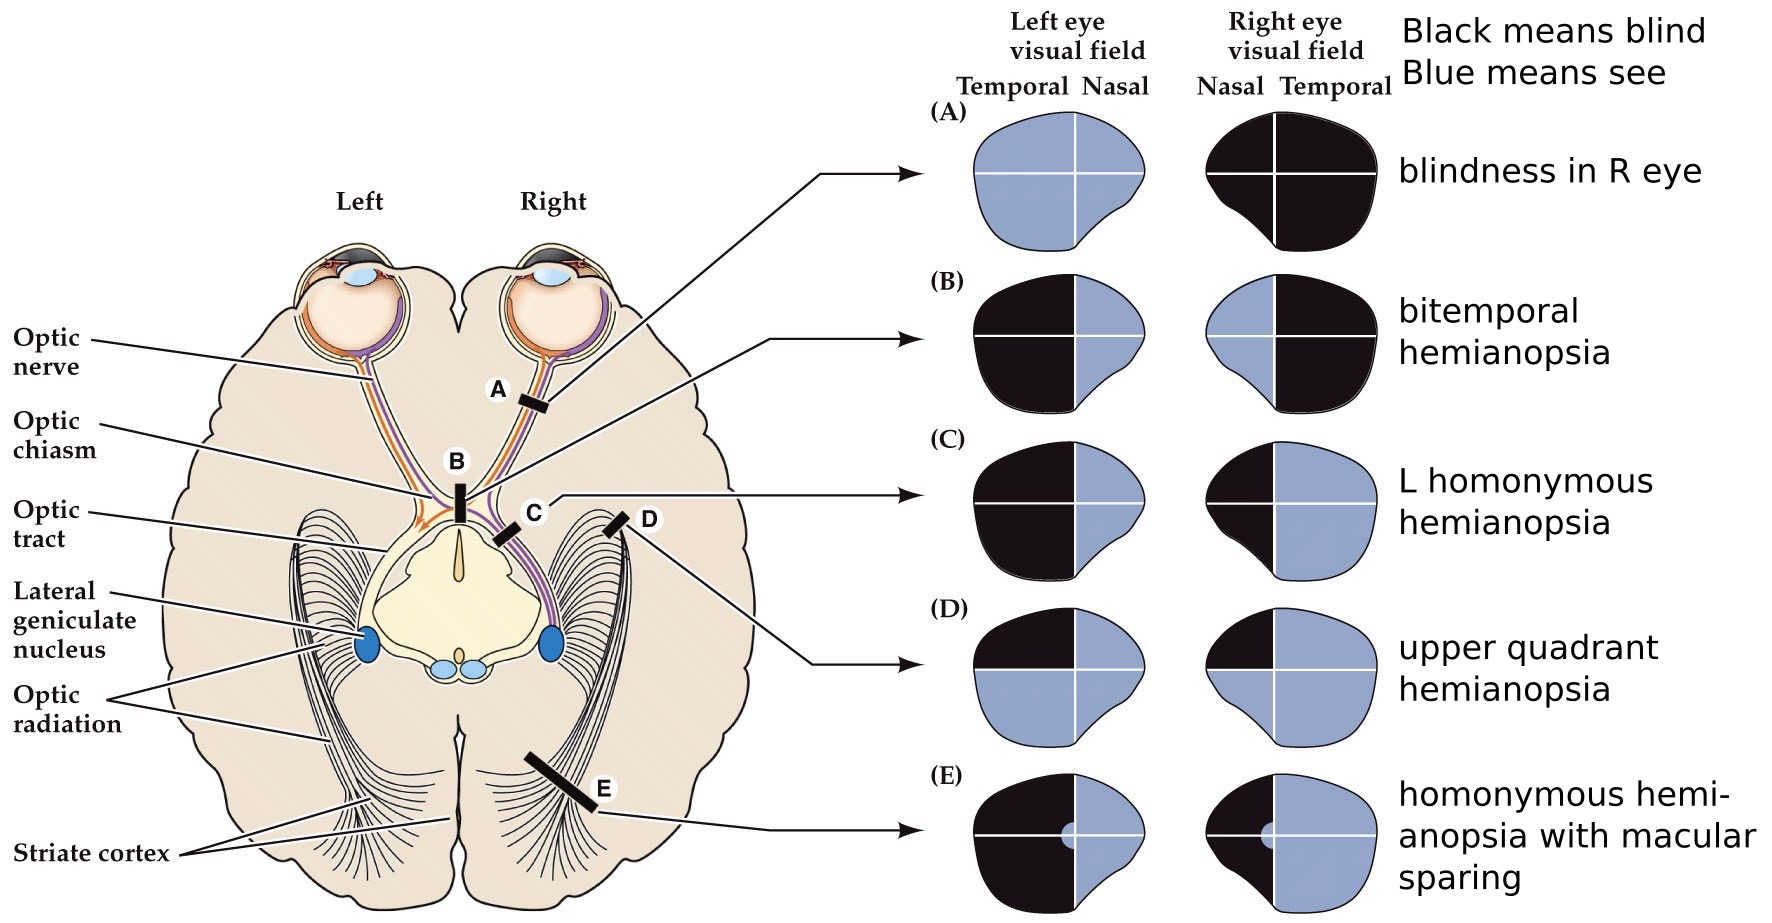

Visual field defects

- The spatial relationships in the retina are maintained in the brain

- Careful analysis of the visual field defects of a patient can often indicate where brain damage is located

- Anopsias— relatively large deficits

- Scotomas— smaller deficits

Visual field deficits resulting from damage along the primary visual pathway

Reasons for macular sparing not known. Has been proposed that there is overlap in the pattern of crossed and uncrossed ganglion cells that provide central vision